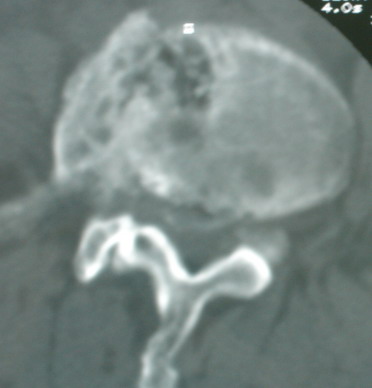

以下是引用卜一在2008-6-3 19:33:00的发言:[br]双肺结节,以双上肺分布为多,期间搀杂片状致密影及索条致密影。考虑:继发性肺结核伴血型播散可能性大。不除外肺泡ca的可能!另:椎体退变!

以下是引用panyishengct在2008-6-3 21:09:00的发言:[br]双上肺弥漫性小结节影,纵隔窗内钙化淋巴结影,考虑矽肺或/和tb可能性较大,不除外肺ca可能。腰椎考虑退变。 [br][br]